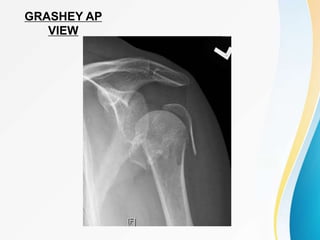

GRASHEY AP

VIEW

• Radiographs :- consist of three views :

• AP- Perpendicular to the plane of scapula(Grashey view)

Taken in neutral arm rotation with torso rotated 30 to 45

degrees